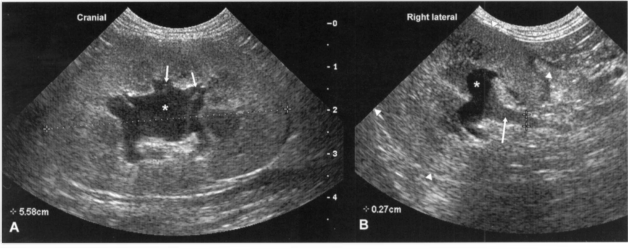

Рис 4. Умеренный гидронефроз. Ультразвуковые изображения правой почки собаки мелкой породы с острой почечной недостаточностью,продольная (А) и поперечная (В) проекции сканирования. Почечная лоханка (*) и рецессусы (показаны короткими стрелками) умеренно дилатированы. Проксимальный отдел мочеточника также умеренно расширен.